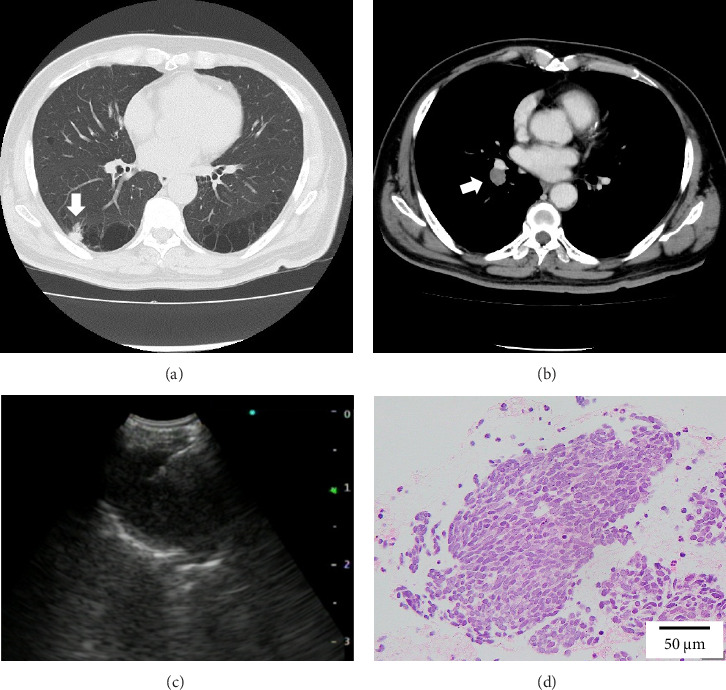

小细胞肺癌(SCLC)合并囊性气隙是罕见的。我们描述的情况下,68岁的男子谁被转介到我们医院,因为在胸部x线检查发现囊性病变。最初的计算机断层扫描显示右下叶膈旁肺气肿引起的小结节邻近囊性空域。组织病理学检查淋巴结病变提示SCLC。化疗后,复发表现为厚壁囊性空腔,囊肿壁有外生结节,类似肺炎。额外的化疗,而不是抗生素治疗,导致壁厚和结节的减少。该病例强调了对抗生素治疗的无反应性,特别是在具有危险因素的患者中,突出了可能延迟及时癌症治疗的诊断陷阱。

Small-cell lung carcinoma (SCLC) associated with cystic airspaces is rare. We describe the case of a 68-year-old man who was referred to our hospital because of a cystic lesion detected on chest radiography. Initial computed tomography revealed a small nodule abutting the cystic airspace due to paraseptal emphysema in the right lower lobe. Histopathological examination of lymphadenopathy indicated SCLC. Postchemotherapy, recurrence appeared as a thick-walled cystic airspace with an exophytic nodule along the cyst wall, mimicking pneumonia. Additional chemotherapy, but not antibiotic therapy, led to a reduction in the wall thickness and nodules. This case emphasizes unresponsiveness to antibiotic therapy, especially in patients with risk factors, highlighting the diagnostic pitfall that may delay timely cancer treatment.